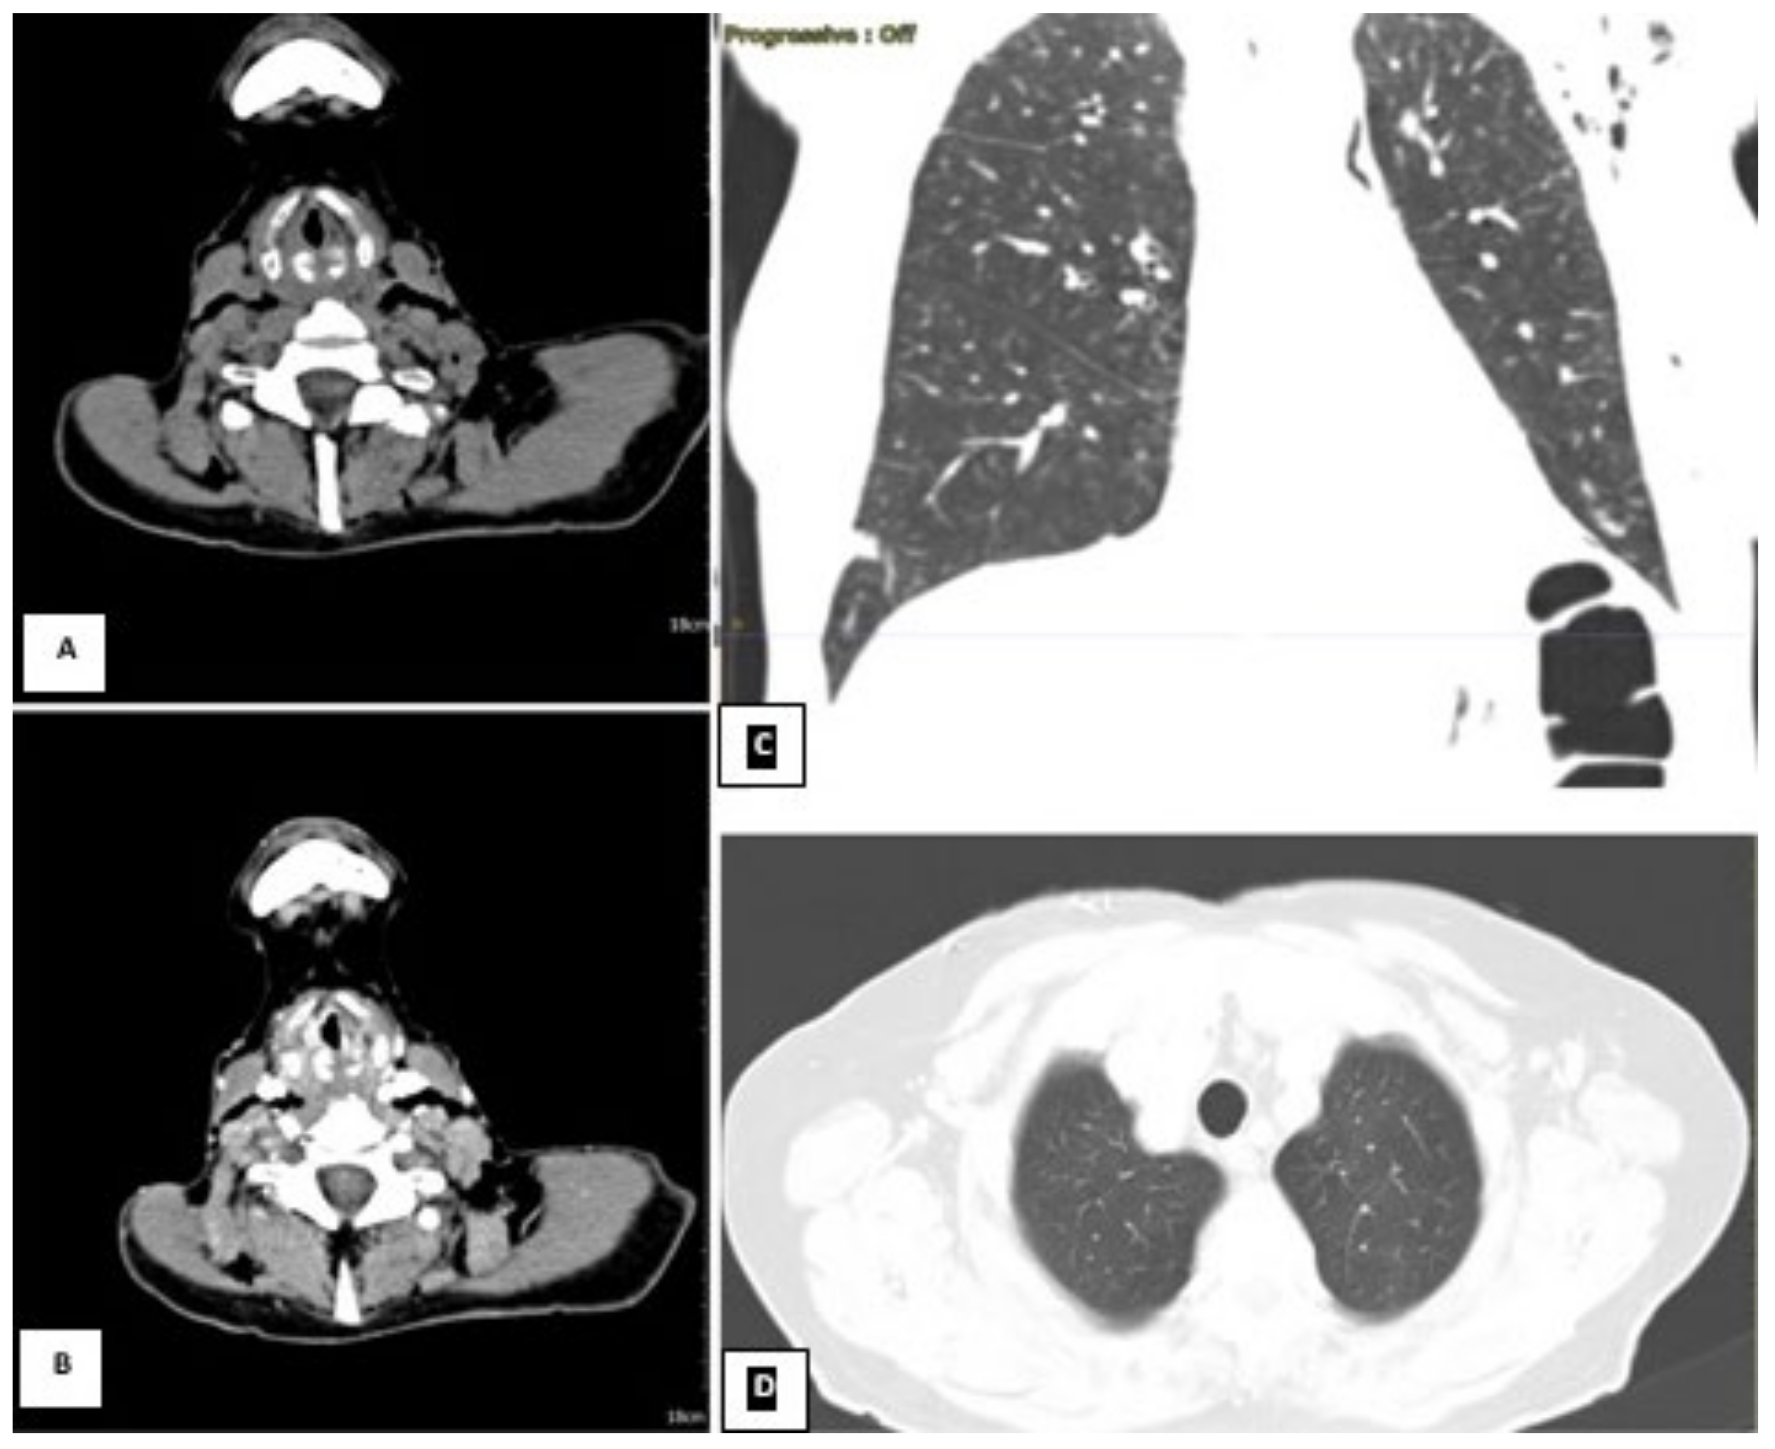

CT scan on the left. The neck scan revealed the presence of small submucosal bilateral glottic masses, associated with increased cervical lymph node volume, without subglottic and extra laryngeal extensions. (A) Axial section basal CT scan on the left. (B) Axial contrast-enhanced CT on the right. Lung window showing a small scar at the level of the right lower lobe from previous pneumonia reported by the patient; (C) coronal and (D) axial lung window). Due to the worsening conditions, the patient was mechanically ventilated because of acute respiratory failure. Despite the therapy and mechanical ventilation, the pulmonary functions deteriorated progressively, resulting in the patient’s death. The patient was not diabetic, hypertensive, or cardiopathic and was not a smoker. By anamnestic clinical history, we discovered that two years before this event (October 2019), the subject presented mild hoarseness of voice. At the time, an endoscopic laryngeal examination revealed bilateral mobile vocal folds without apparent abnormalities. For further confirmation, the subject underwent a laryngeal exam under general anesthesia, which showed the absence of any macroscopic lesion, and the histopathological results of the biopsies were negative. The physicians scheduled a follow-up after three months, but unfortunately, the lockdown caused by the COVID-19 pandemic and the fear of viral infection prevented her to attend the recommended follow-up visits. The patient was COVID-19-negative throughout the whole illness (Table 1). We performed a literature analysis by searching the PubMed database for ‘laryngeal adenoid cystic carcinoma’. We did not limit the search to article types because of the rarity of the disease and the little number of papers about it. We choose only papers published in English within the past five years. The articles in the database whose full text could not be found were also excluded. The title and abstracts of the identified manuscripts were initially screened and selected by all authors independently (IF, AC, PGM, HE, RA, MF, MR, DM, AG, MdV, CB, and AM) based on their relevance to the review topic. The following set of shared chosen inclusion criteria was applied individually to the selected articles in their full-text version: primary laryngeal affection of adenoid cystic carcinoma and therapy consensus of LACC. The literature search yielded 48 papers. Subsequently, 28 studies were excluded because they did not meet the objective of our review, and 20 studies were included and discussed (Figure 5 and Table 2).